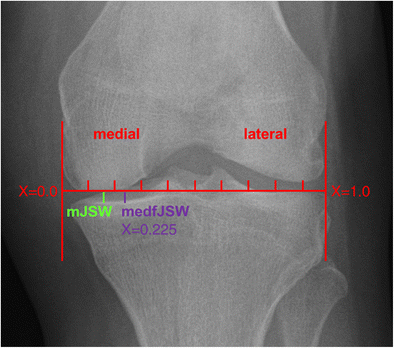

Quantitative joint space width measures

Weight-bearing, posterior-anterior fixed-flexion (10°) radiographs were acquired from OAI participants at each annual visit [18, 23]. Semi-automated radiographic JSW measurements were performed for the majority of these knees [9, 10] (Fig. 2). In the current study, we analysed medial compartment mJSW and medial compartment fixed-location JSW at 22.5% of the mediolateral width of the distal femur [medial fixed-location (medf)JSW, Fig. 2] [9] as this measure has been previously shown to display greater sensitivity to change in KOA [10, 24] and a stronger relationship with subsequent KR than mJSW [2].

radiographic joint space width. Fixed-flexion radiograph depicting the medial to lateral coordinate system used for fixed-location measurement (medfJSW: medial fixed joint space width at 22.5%), as well as the minimum medial joint space width (mJSW)